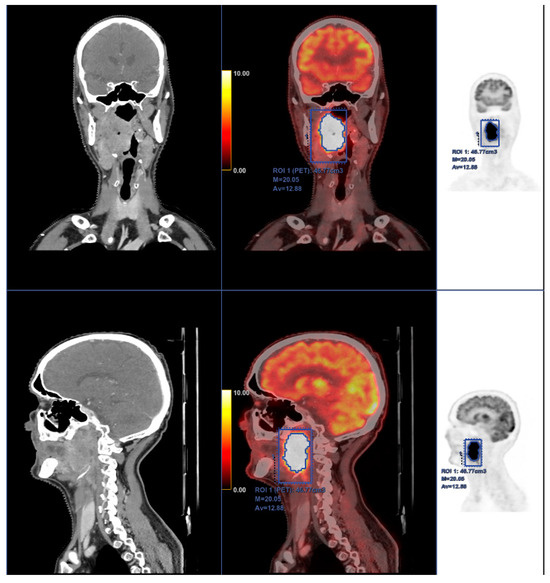

Segmentation of the primary tumors was performed using the LIFEx v6.30 software (https://www.lifexsoft.org (accessed on 9 February 2024) [27]. An initial volume encompassing the whole tumor was manually drawn on the [18F]FDG PET images according to clinical data. Images were read by an experienced nuclear medicine physician (example in Figure 2). Specifically, the SUVmax from the corresponding initial clinical records was used to distinguish the primary lesion from secondary lymph nodes. The segmentation of the tumor, i.e., the primary lesion, was computed applying a threshold of 41% of the SUVmax inside the previously drawn volume [28], obtaining the volume of interest (VOI). LIFEx was set up using the following input parameters for calculation of textural features: 64 gray levels for intensity discretization; and absolute resampling between a minimum of 0 and a maximum of 39 (the maximum SUV of the segmented VOIs for the whole study cohort) for intensity rescaling [29]. A total of 48 features were extracted. These included 13 conventional parameters, 4 shape and size features, 6 second-order textural features (from the gray-level co-occurrence matrix, GLCM), and 25 third and higher order textural features (3 from the neighborhood gray-level different matrix, NGLDM; 11 from the gray-level run-length matrix, GLRLM; and 11 from the gray-level zone-length matrix, GLZLM) [30,31,32,33]. Shape and size features include the MTV, Sphericity, Compacity, and Surface. Texture indices were computed for each of the gray-level matrixes mentioned above.

Figure 2.

Fifty-eight-year-old male with squamous cell carcinoma of the right tonsil, which is shown to invade adjacent spaces of the oropharynx; especially significant is the invasion of muscular and adipose tissue nearby. Moreover, the tumor causes a reduction of the airway diameter. Intense and homogeneous [18F]FDG uptake is seen in all the malignant tissue as usually identified in these tumors. PET-CT in this case was also used for radiotherapy planning and as a basal study for therapeutic response in subsequent studies.